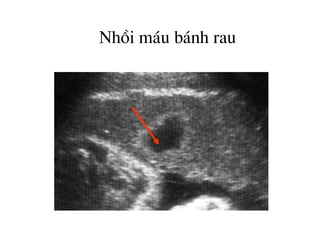

Nhåi m¸u b¸nh rau

Tô m¸u trong nhu m« rau